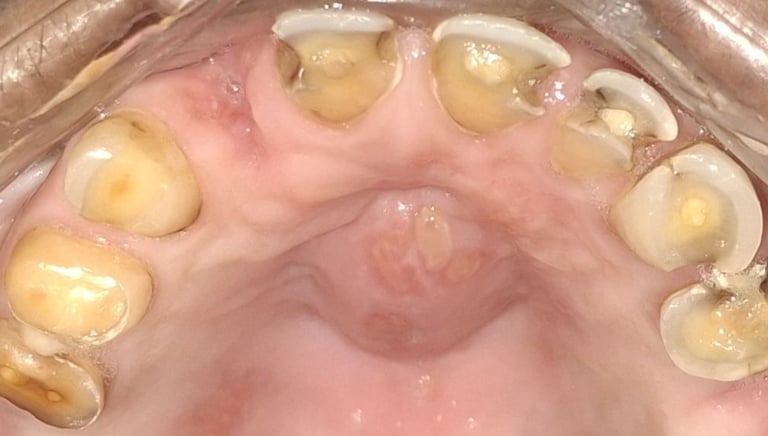

Clinical pictures of teeth requiring RCT

All images are of real cases of teeth where Root canal treatment was performed to remove infection and preserve the natural tooth restoring normal chewing and function of teeth.